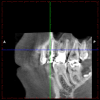

Born486 Опубликовано 23 мая, 2012 Поделиться Опубликовано 23 мая, 2012 Добрый вечер. Хотел бы получить совет специалистов. Интерисуют зубы под №14, 15, 16. Зубы не болят, но довольно сильно разрушены (были большие пломбы со штифтами, но со временем сломались стенки зубов (№15,16), лечение проводилось от 2-5 лет назад.Рекомендации от врачей:15 - зуб первый кандидат на удаление.16 - удаление или перепломбировка каналов (при помощи ультразвука) , резекция верхушки корня, штифтовкладка.14 - пока под вопросом.Ну вот как-то так! Ссылка на комментарий

kriokov Опубликовано 23 мая, 2012 Поделиться Опубликовано 23 мая, 2012 по КТ - 16 и 15 удалил бы. Ссылка на комментарий

Born486 Опубликовано 24 мая, 2012 Автор Поделиться Опубликовано 24 мая, 2012 16 -полностью перебрать.Сохранить можно.15 - 99.9% удалять14 - перебрать. Спасибо, за ответы, но хотелось бы подробнее про 15 зуб (какие видно проблемы по КТ) и 16 зуб насколько целесообразно сохранять его, сколько он может прослужить из Вашего опыта востановления подобных зубов (т.к. стоимость лечения выходит около 80-85% от стоимости установки имплантанта “под ключ”). Ссылка на комментарий